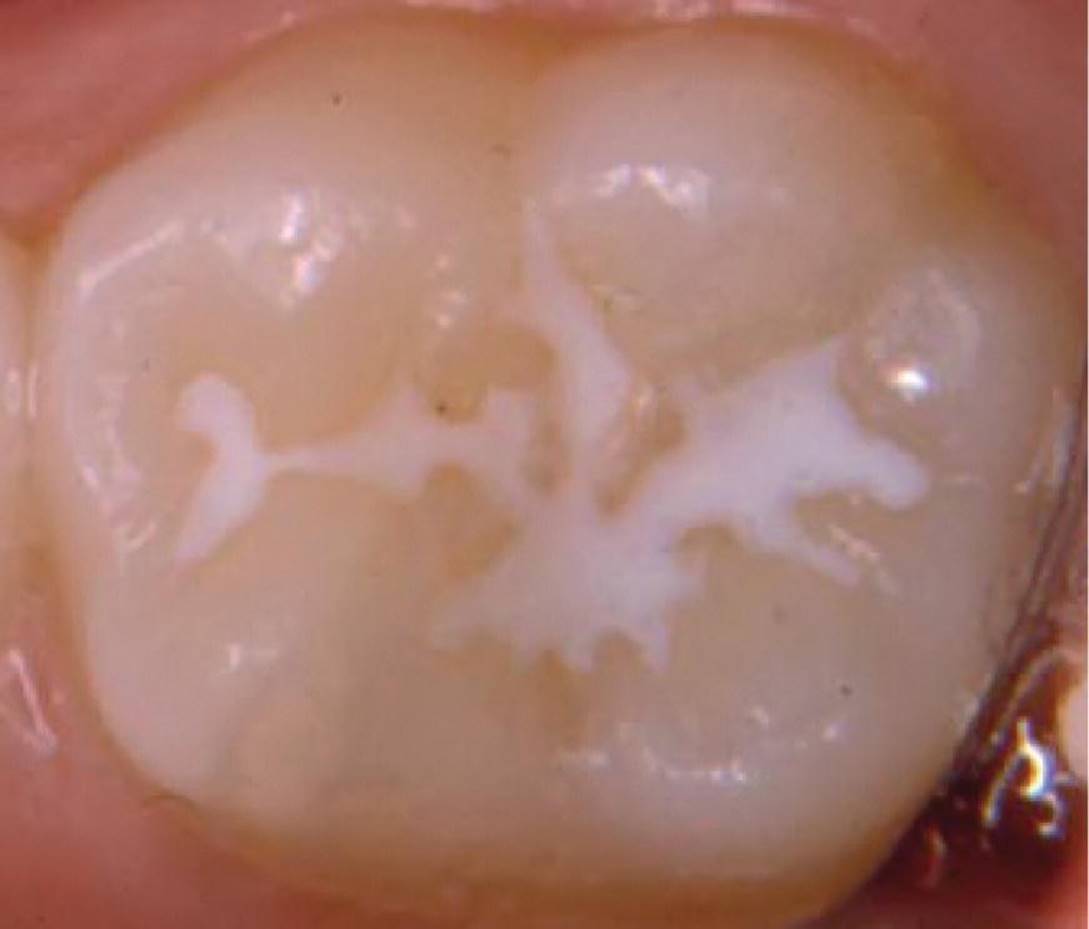

Figure 12.20 Fissure sealing covering all parts of the fissure without overfilling and overextension.

Fissure sealing is a method where the fissure systems or pits are sealed with a material that is retained on the enamel surface either by the acid‐etch technique (resin sealants) or through chemical bonding (GIC sealants). Since the technique was introduced in the late 1960s, based on resins and the acid‐etch technique, a variety of methods for the prevention, nonoperative treatment of noncavitated lesions, and restoration of pit and fissure caries have been developed in its wake [98]. In this textbook, the term fissure sealing applies to techniques for pits and fissures that are either caries free or only have initial caries lesions without cavity formation, and where the removal of soft carious tissue is not advocated. Preventive restoration is the term used for a combined restorative and sealing procedure.

Fissure sealing